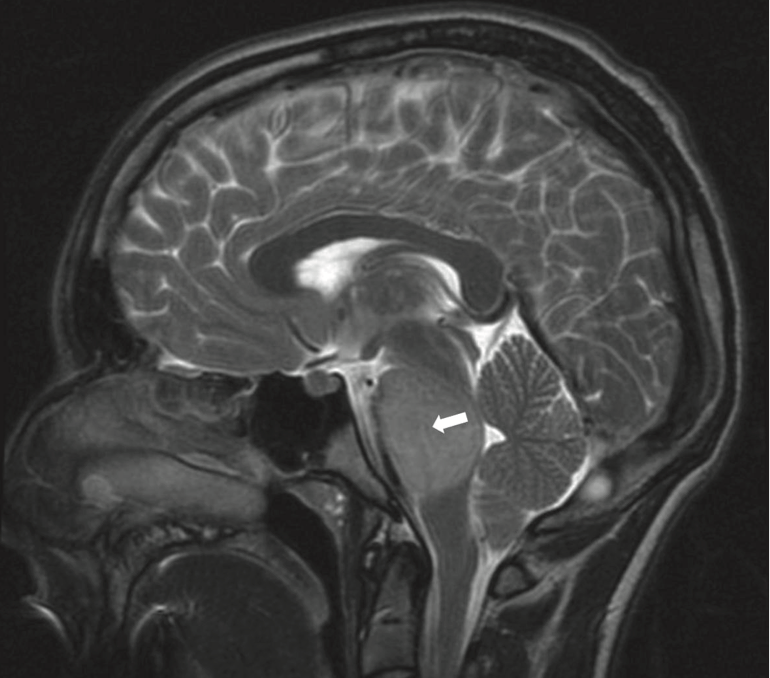

小儿脑干胶质瘤怎么诊断 儿童脑干胶质瘤可通过颅脑CT进行、磁共振和活检等检查和诊断。儿童通常会出现行走不稳、言语不清等症状。CT检测时,会发现...